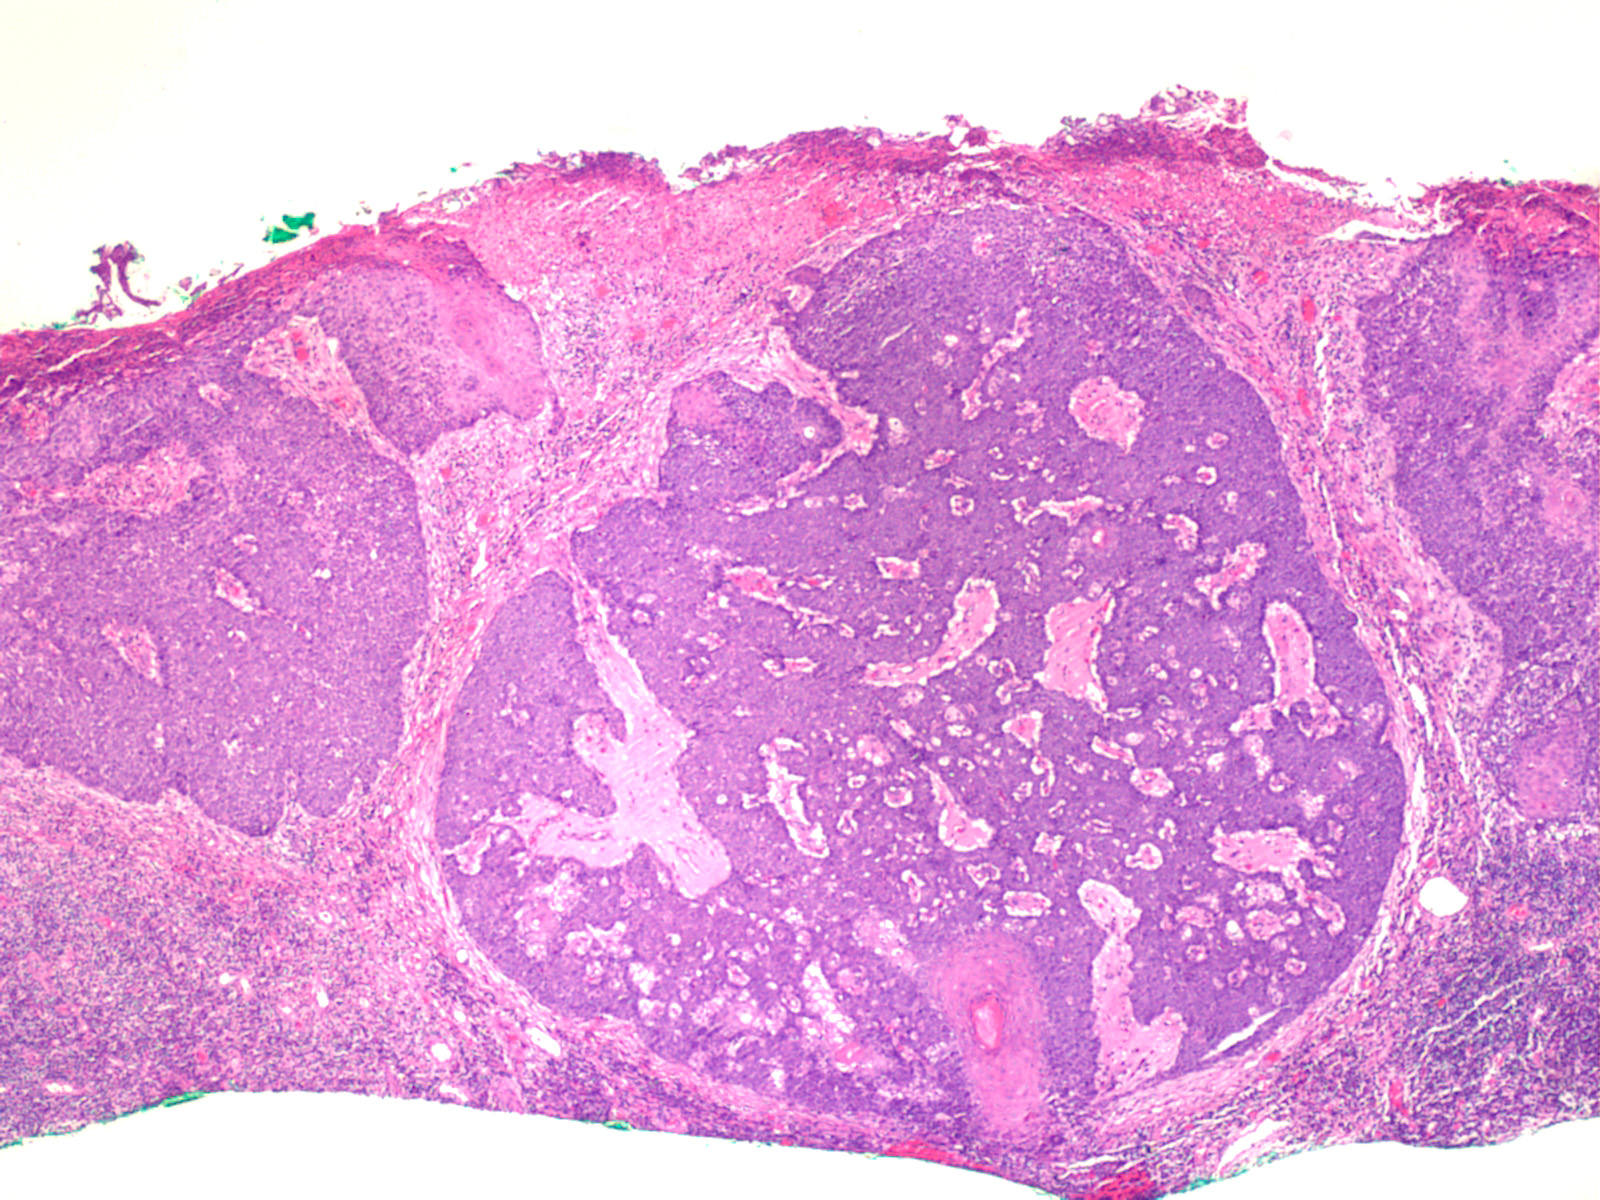

Sebaceous carcinoma = الكارسينوما الدهنية

OLYMPUS DIGITAL CAMERA